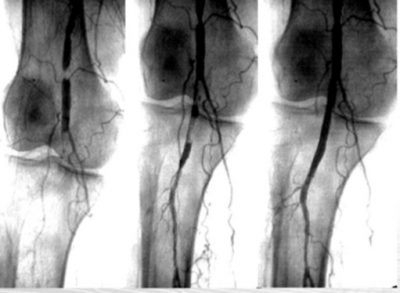

قسطره تفتيت الجلطات الشريانيه “الروتاريكس”

تعمل قسطرة تفتيت الجلطات (الروتاريكس) لإزالة الجلطات الشريانية عن طريق:

١- خلخلة الجلطة من خلال الذبذبة الدائرية

٢- تفتيت الجلطة

٣-شفط الجلطة المفككة

٤-ازله الجلطة من الشريان

ويظهر دور هذه القسطره في:

-الجلطات الحديثه في شرايين الساق و جلطالت الانصمام

-في بعض النسدادات المزمنه ذات التكلسات العنيفه اوالترسبات المتقدمه

-انسدادات الشرايين الصناعيه الجراحيه

-الدعامات الطرفيه المغلقه